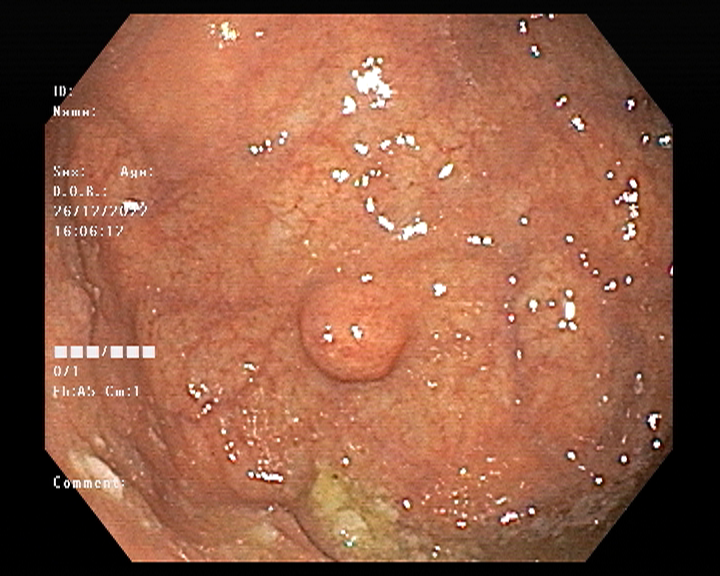

Endoscopy and colonoscopy are safe and accurate procedures used to directly examine the digestive tract and detect the root cause of chronic acidity, GERD, abdominal pain, bleeding, and bowel irregularities. These minimally invasive tests help identify ulcers, inflammation, infections, polyps, strictures, and early cancerous changes.

At Sapphire Gastroenterology Center, modern endoscopic equipment ensures precise diagnosis and, when required, therapeutic intervention during the same procedure. Based on findings, targeted treatment plans are created, including medication, diet guidance, and preventive strategies. Early diagnosis through endoscopy and colonoscopy plays a crucial role in preventing serious complications and improving long-term digestive health.